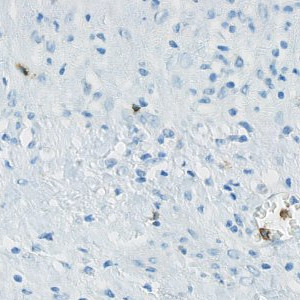

Selected view of ovarian CD57 stained tissue.

Natural Killer (NK) cells are a subtype of lymphocytes. They hold anticancer potential through tumor cell lysing and their prognostic role is being investigated in many cancers, with a perspective of a therapeutic potential. The prognostic role of tumor infiltrating NK cells in ovarian cancer, is being investigated at the Department of Clinical Pathology, Vejle Sygehus.

This APP can be used to evaluate the number or density of CD57 positive nuclei.

A NK positive cell is detected as a haematoxylin stained nucleus surrounded by DAB membrane stain. Initially, the protocol detects haematoxylin stained nuclei surrounded by brown stain using a poly blob filter on the H&E haematoxylin band and a median filter on the HDAB-DAB band. The DAB membrane stain is emphasized by a mean unsharp filter, thereby excluding blurry background stain. Then, positive nuclei are detected based on size, shape, and amount of surrounding DAB stain. Final NK cells are seen in FIGURE 2.